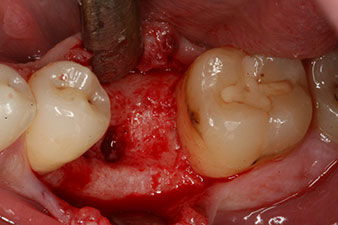

Фиг. 2: Шест седмици по-късно в областта на корена мезиално има непълно осифицирана алвеола.

Шест седмици след екстракцията се открива непълна осификация след препарацията на мукопериосталното ламбо в областта на предходната алвеола мезиално.

Имплант

Фиг. 3: След препарация с имплантологичния мотор Implantmed, е поставен имплант (диаметър 4 mm, дължина 12 mm) при въртящ момент от 43 Ncm.

Имплантът е поставен както е планирано след цялостно отстраняване на гранулационната тъкан (blueSky, bredent).